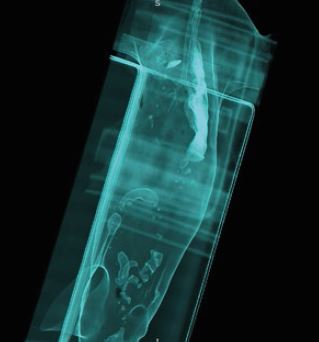

КТ-ангіографія

Чіткі, різкі зображення з високою роздільною здатністю необхідні для встановлення найточнішого діагнозу. А швидке отримання та інтерпретація оптимізує робочий процес і має важливе значення в екстрених ситуаціях. Ви можете досягти високої якості зображення швидше за допомогою багаторядного детектора PUREVision від Aquilion, який має на 40% більшу світловіддачу порівняно з іншими системами. Це єдиний доступний багаторядний детектор з фактичною роздільною здатністю 0,5 мм. Справжня ізотропна роздільна здатність унікального детектора Aquilion PUREVision дозволяє проводити багатоплощинні реконструкції з найвищою просторовою роздільною здатністю у всіх площинах.

Чутлива технологія управління контрастом забезпечує стабільно високу якість результатів для діагностики різних судинних захворювань. Технологія SEMAR (Single Energy Metal Artifact Reduction) від Canon Medical мінімізує артефакти від металу та покращує візуалізацію імплантатів, опорної кістки та прилеглих м'яких тканин. Передові технології Canon Medical для комп'ютерного томографа Aquilion включають методи адаптивного ітеративного зменшення дози 3D (AIDR 3D) та вдосконалену інтелектуальну реконструкцію з глибоким навчання Clear-IQ Engine (AiCE) (DLR). Ця виняткова реконструкція на основі штучного інтелекту значно знижує рівень шуму і підвищує SNR (співвідношення сигналу до шуму).